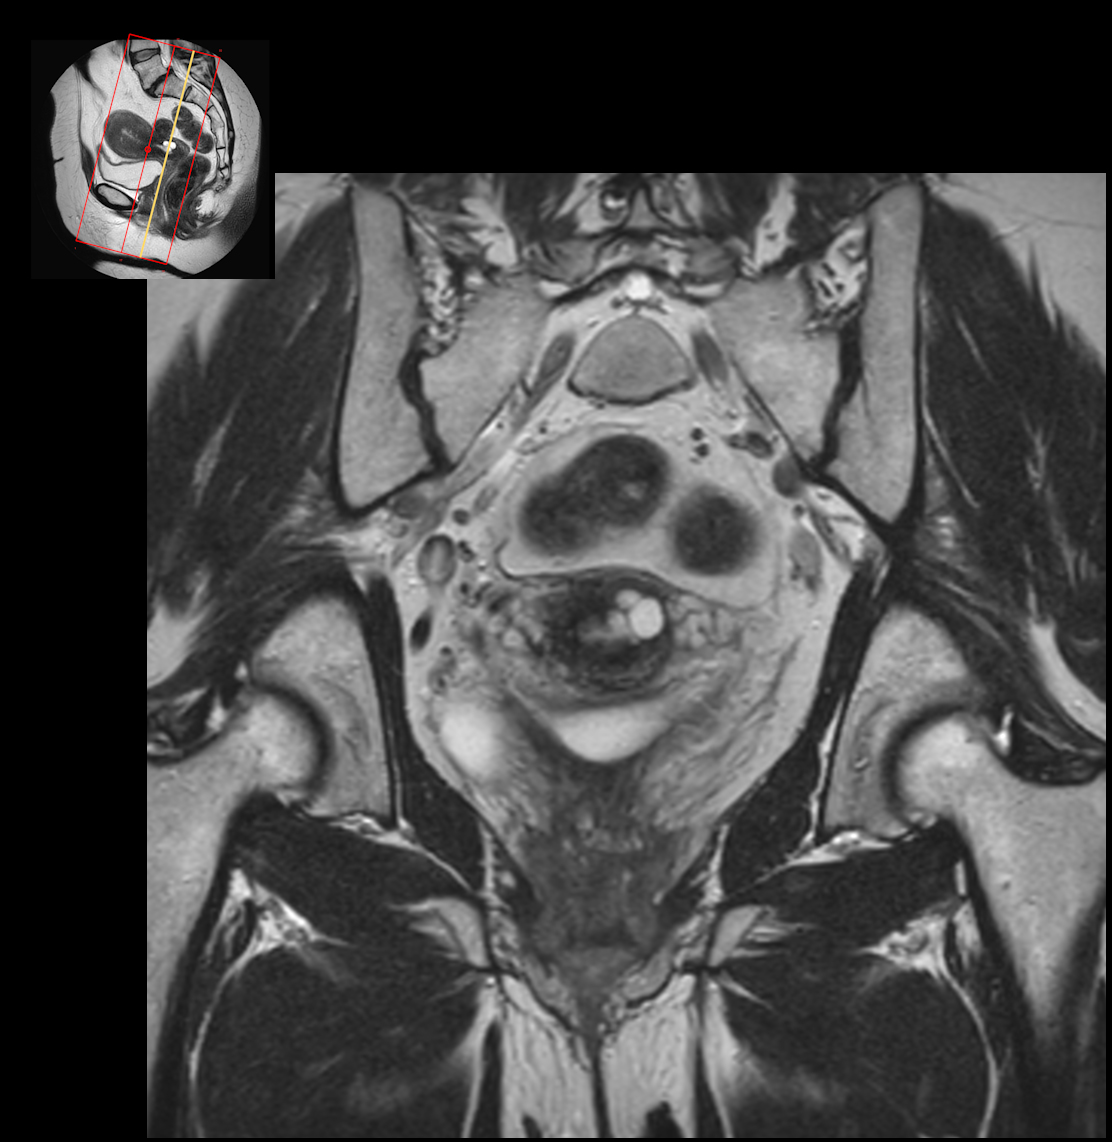

Long axis T2w TSE